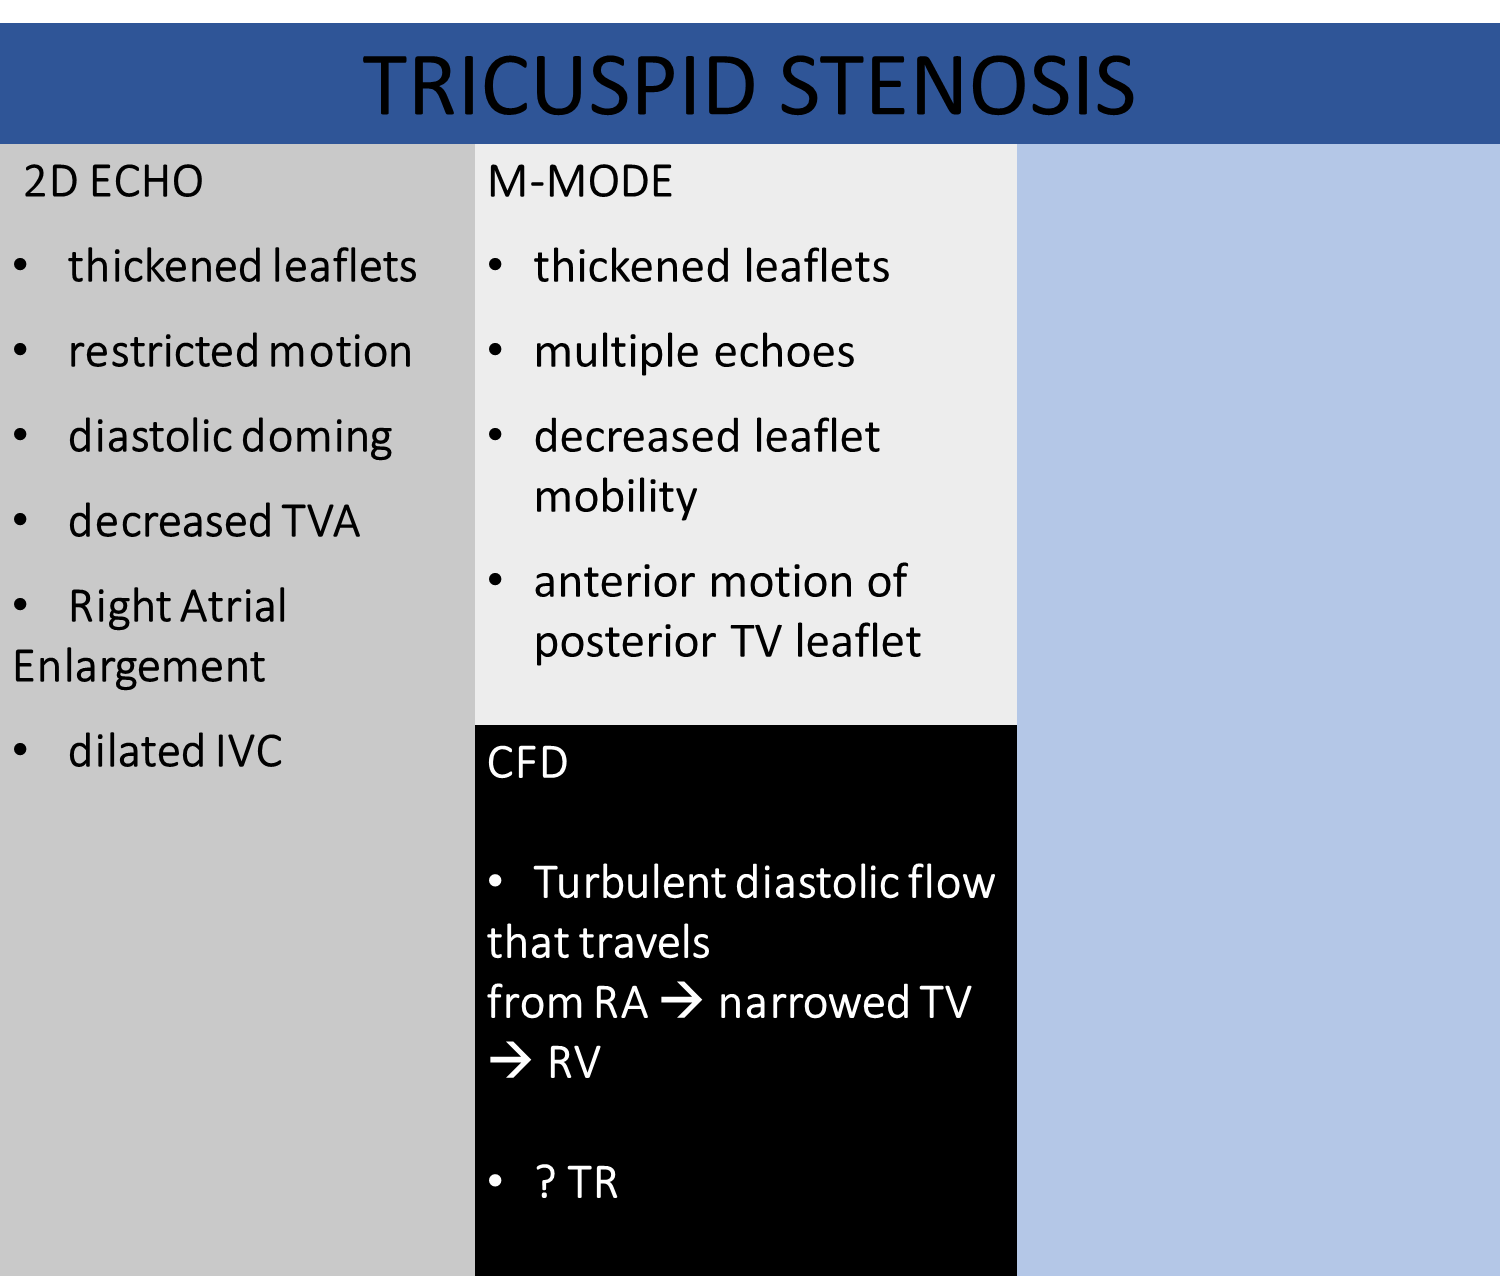

Asses RVIT

Asses apical 4

Asses RVOT in SAX

asses in Spectral doppler

Tv Inflow (PW)

RV inflow pattern

PWD gate at tips of TV leaflets

Normal Flow is Antegrade

Use TV package (E/A velocity)

Measure peak E velocity and Decel slope

>1 m/s suggestive of high velocity

2. Measure peak A wave

TV stenosis (CW)

DECREASED E-F SLOPE

OBTAIN TVA USING

PHT METHOD

NORMAL TVA 7-9 CM

TRACE E & A WAVE TO OBTAIN MEAN PG

Severity Scale